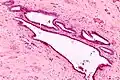

| Transvaginal ultrasound showed cystic formations in the areas of the right fallopian tube (a) and fundus uteri (b), (c); uterus (front) with right tube and right abdominal wall (background). | |